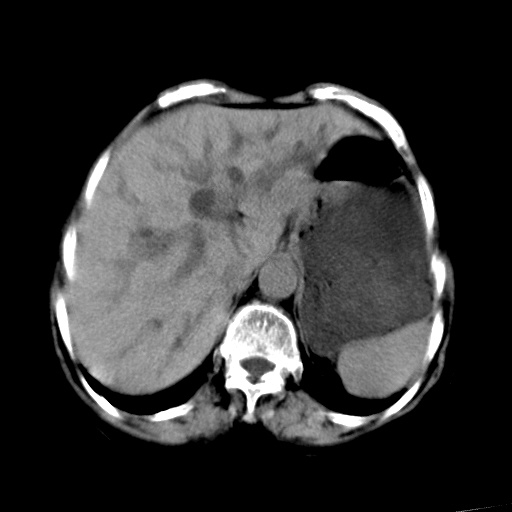

以下是引用杀毒软件在2009-3-4 17:38:00的发言:[br]为何没有喝照影剂呀? 胆总管及肝内胆管扩张,增强吧。[br][br]考虑-----十二指肠占位----建议----十二指肠镜检查[br][br]

以下是引用jiangjing在2009-3-4 17:45:00的发言:[br]低位胆道梗阻。十二指肠降段局部管壁增厚。扫描效果不理想,建议ct增强及ercp。

以下是引用杀毒软件在2009-3-4 17:38:00的发言:[br]为何没有喝照影剂呀? 胆总管及肝内胆管扩张,。增强吧。[br][br]考虑-----十二指肠占位----建议----十二指肠镜检查[br][br][br][br][本贴已被 杀毒软件 于 2009-3-4 17:56:38 修改过]